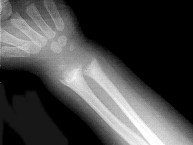

男,2岁,关节肿胀,结合图像,最可能的诊断是()

• A.肾性骨病

• B.黏多糖贮积症

• C.维生素D缺乏症

• D.维生素C缺乏症

• E.维生素D过多症